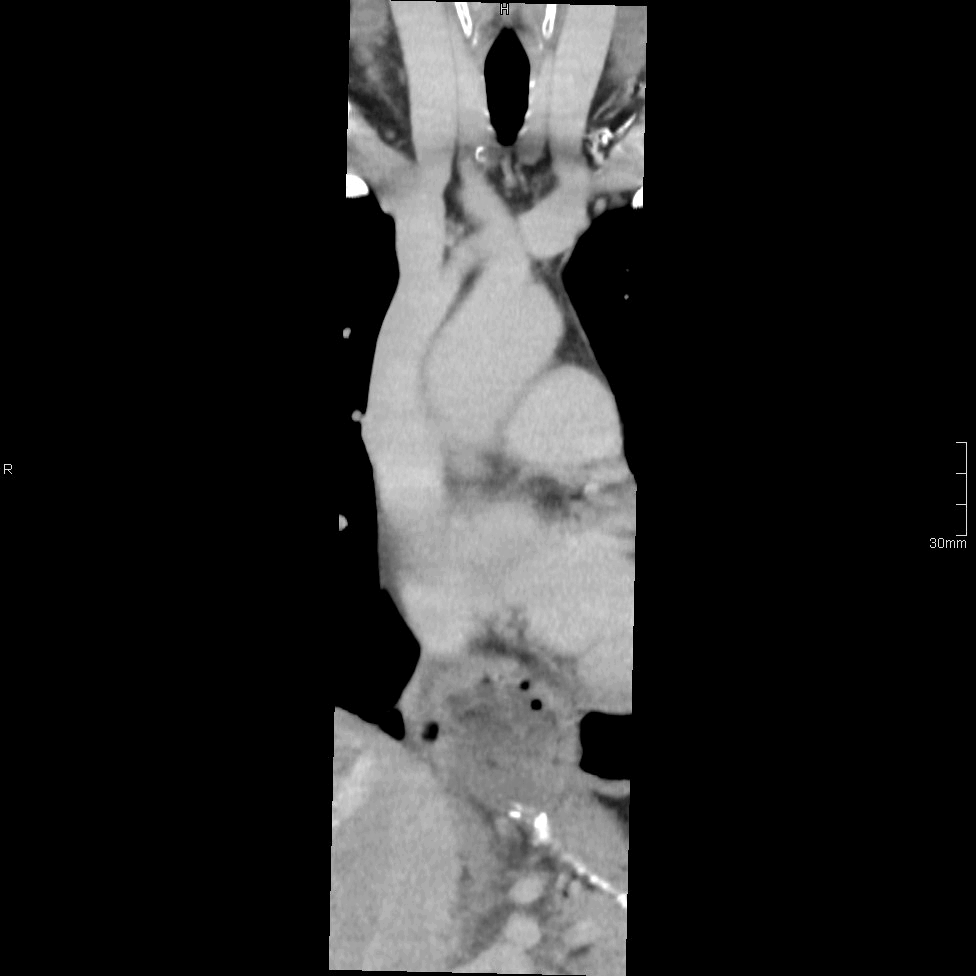

CT Thoracic Spine Contrast- Soft tissue window (coronal)